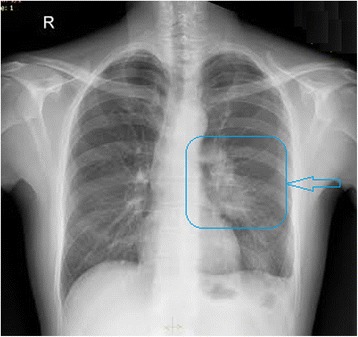

Subsequently, chest X-ray (CXR) showed obliteration of the left costophrenic angle and increased inhomogenous density in the left perihilar zone (Figure 3).

Figure 3.

Chest X-ray showed obliteration of the left costophrenic angle and increased inhomogenous density in the left parahilar zone.